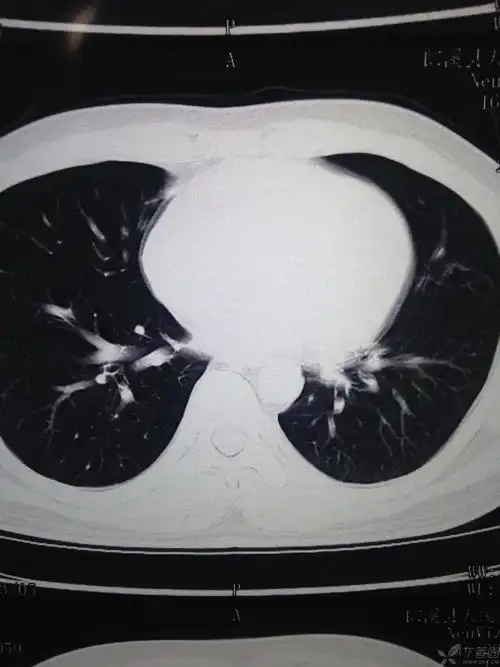

【病例讨论】发热咳嗽咳痰,肺部阴影 [病例帖]

咳嗽3个月,发现肺部阴影1个月

【影像读片】这样的肺部阴影能考虑什么?

【影像读片】肺部阴影求助